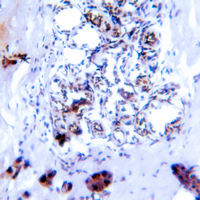

Immunohistochemical analysis of SMAD2/3 (Phospho-T8) staining in human breast cancer formalin fixed paraffin embedded tissue section. The section was pre-treated using heat mediated antigen retrieval with sodium citrate buffer (pH 6.0). The section was then incubated with the antibody at room temperature and detected using an HRP conjugated compact polymer system. DAB was used as the chromogen. The section was then counterstained with haematoxylin and mounted with DPX.